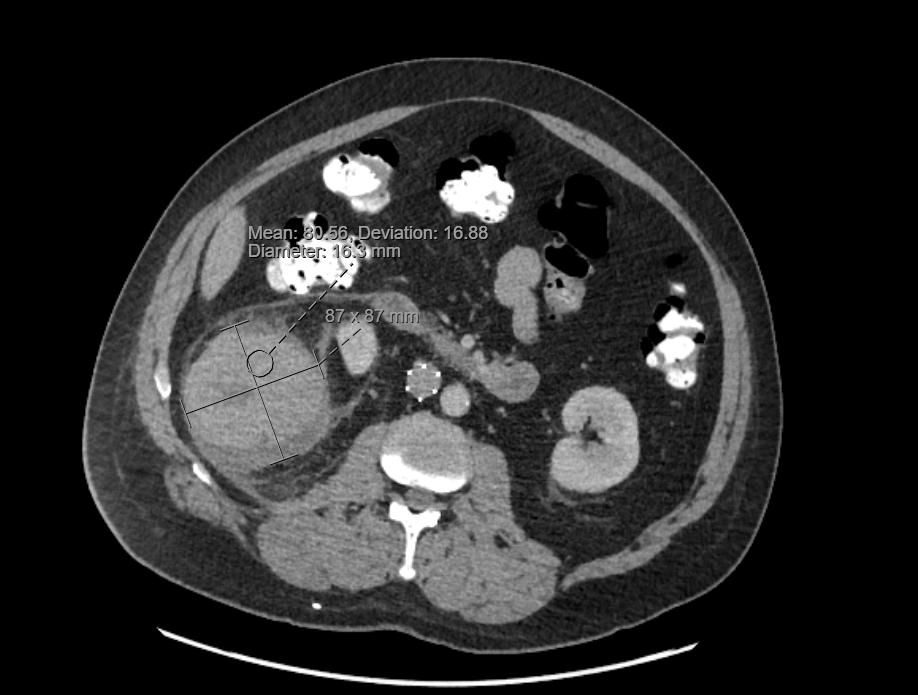

Case Presentation: A 60-year-old man presented with four days of right upper quadrant pain and right flank pain. He had a past medical history that included hypertrophic cardiomyopathy with pacemaker and ICD, hyperlipidemia, atrial flutter, hypertension, prior pulmonary embolism status post IVC filter, and a known renal cyst first identified greater than ten years prior. He had recently returned from a trip to Costa Rica, where he experienced a sudden, severe onset of RUQ abdominal pain with radiation to his right flank. The pain was constant but worse with movement and inspiration and was initially attributed to food poisoning by the patient. He denied any trauma to the region, particularly given that he had chronic difficulty ambulating due to multiple previous femur surgeries; he ambulated with crutches at baseline. He presented to care due to persistent and progressive pain. Vital signs on presentation were BP 131/81, HR 74, Temp 37.1°C, RR16. Physical exam was notable for RUQ tenderness to deep palpation and notable absence of costovertebral angle tenderness or skin discoloration/ecchymosis. Laboratory findings were notable for leukocytosis of 14.4 x1,000/uL and an initial hemoglobin of 10.1 g/dL from baseline of 12 g/dL. CT imaging showed a heterogeneously hyper-dense lesion in the lower pole of the right kidney measuring up to 9.9cm in size with surrounding stranding and fluid in the right perinephric space, likely reflecting the sequelae of a ruptured hemorrhagic renal cyst though solid component could not be excluded. Confirmation with MRI was delayed due to concerns regarding the patient’s pacemaker and retained spinal stimulator leads. He was normotensive and his hemoglobin remained stable through admission, and he was discharged with plans for outpatient MRI and nephrology evaluation.